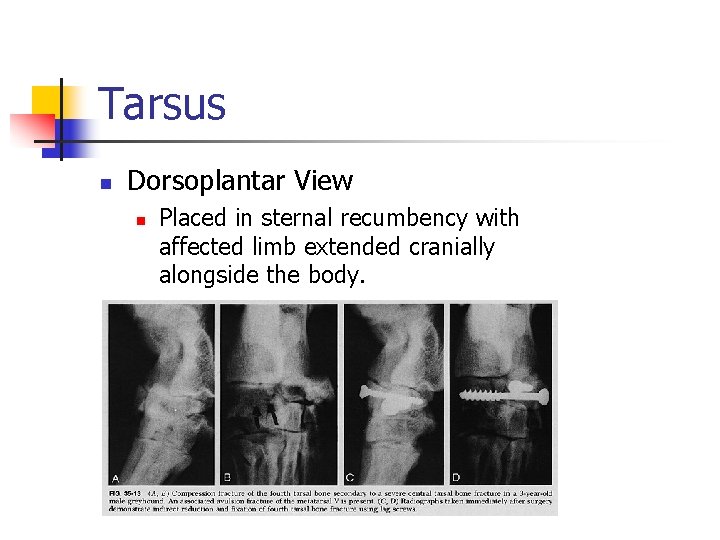

Tarsus n Dorsoplantar View n Placed in sternal recumbency with affected limb extended cranially alongside the body.